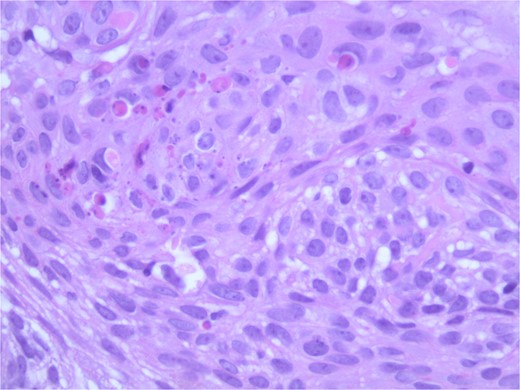

At the time of the surgery, the lesion was excised with 5 mm margins, given the acceptable margins of 4 mm for nonmelanoma skin cancer [4]. Macroscopic examination of the lesion revealed a well-defined, hyperpigmented, macular lesion with pathology positive for infiltrating BSC with negative margins confirmed on histology. Histology was notable for predominantly basal cell morphology with areas of squamous differentiation. The presence of the basal cell carcinoma component is demonstrated (Fig. 1). The BSC with abnormal squamous keratinization is also demonstrated (Figs 2–4). These studies were conducted on routine hematoxylin and eosin stains confirming the diagnosis of BSC. The patient was seen in the office, and at 2 months postoperative, there were no clinical concerns.

Microphotograph revealing basal cell carcinoma component on histology.